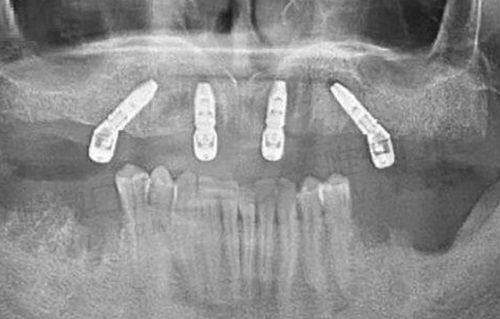

医院设备与技术:数字化升级的口腔新体系

广州雅致口腔门诊部对于设备投入非常注重“实时精细”和“数字化”体验结合。其内部配备有德国卡瓦种植机、3D口腔CT、CAD/CAM椅旁全瓷修复系统、数字化口腔内窥镜、激光治疗仪等配置,尤其在种植体计划设计和正畸模拟方面,采用可视化操作,患者在治疗初期即可看见预估成效,不仅提升了决策信心,还增加了治疗可控制性。

雅致口腔目前已开展项目包括但不限于:种植牙、牙齿矫正、牙体牙髓病、儿童齿科、牙齿修复、牙周治疗、口腔美容、微创拔牙等。诊所尤以数字化种植系统和金属自锁托槽矫正系统受到好评,不少患者反馈种植牙术后舒适度高、修复快。而在儿童齿科领域,广州雅致口腔门诊部专门设置温馨色调的儿童诊室,不同卡通装饰墙面营造无压氛围,是本地家长带娃常选之地。